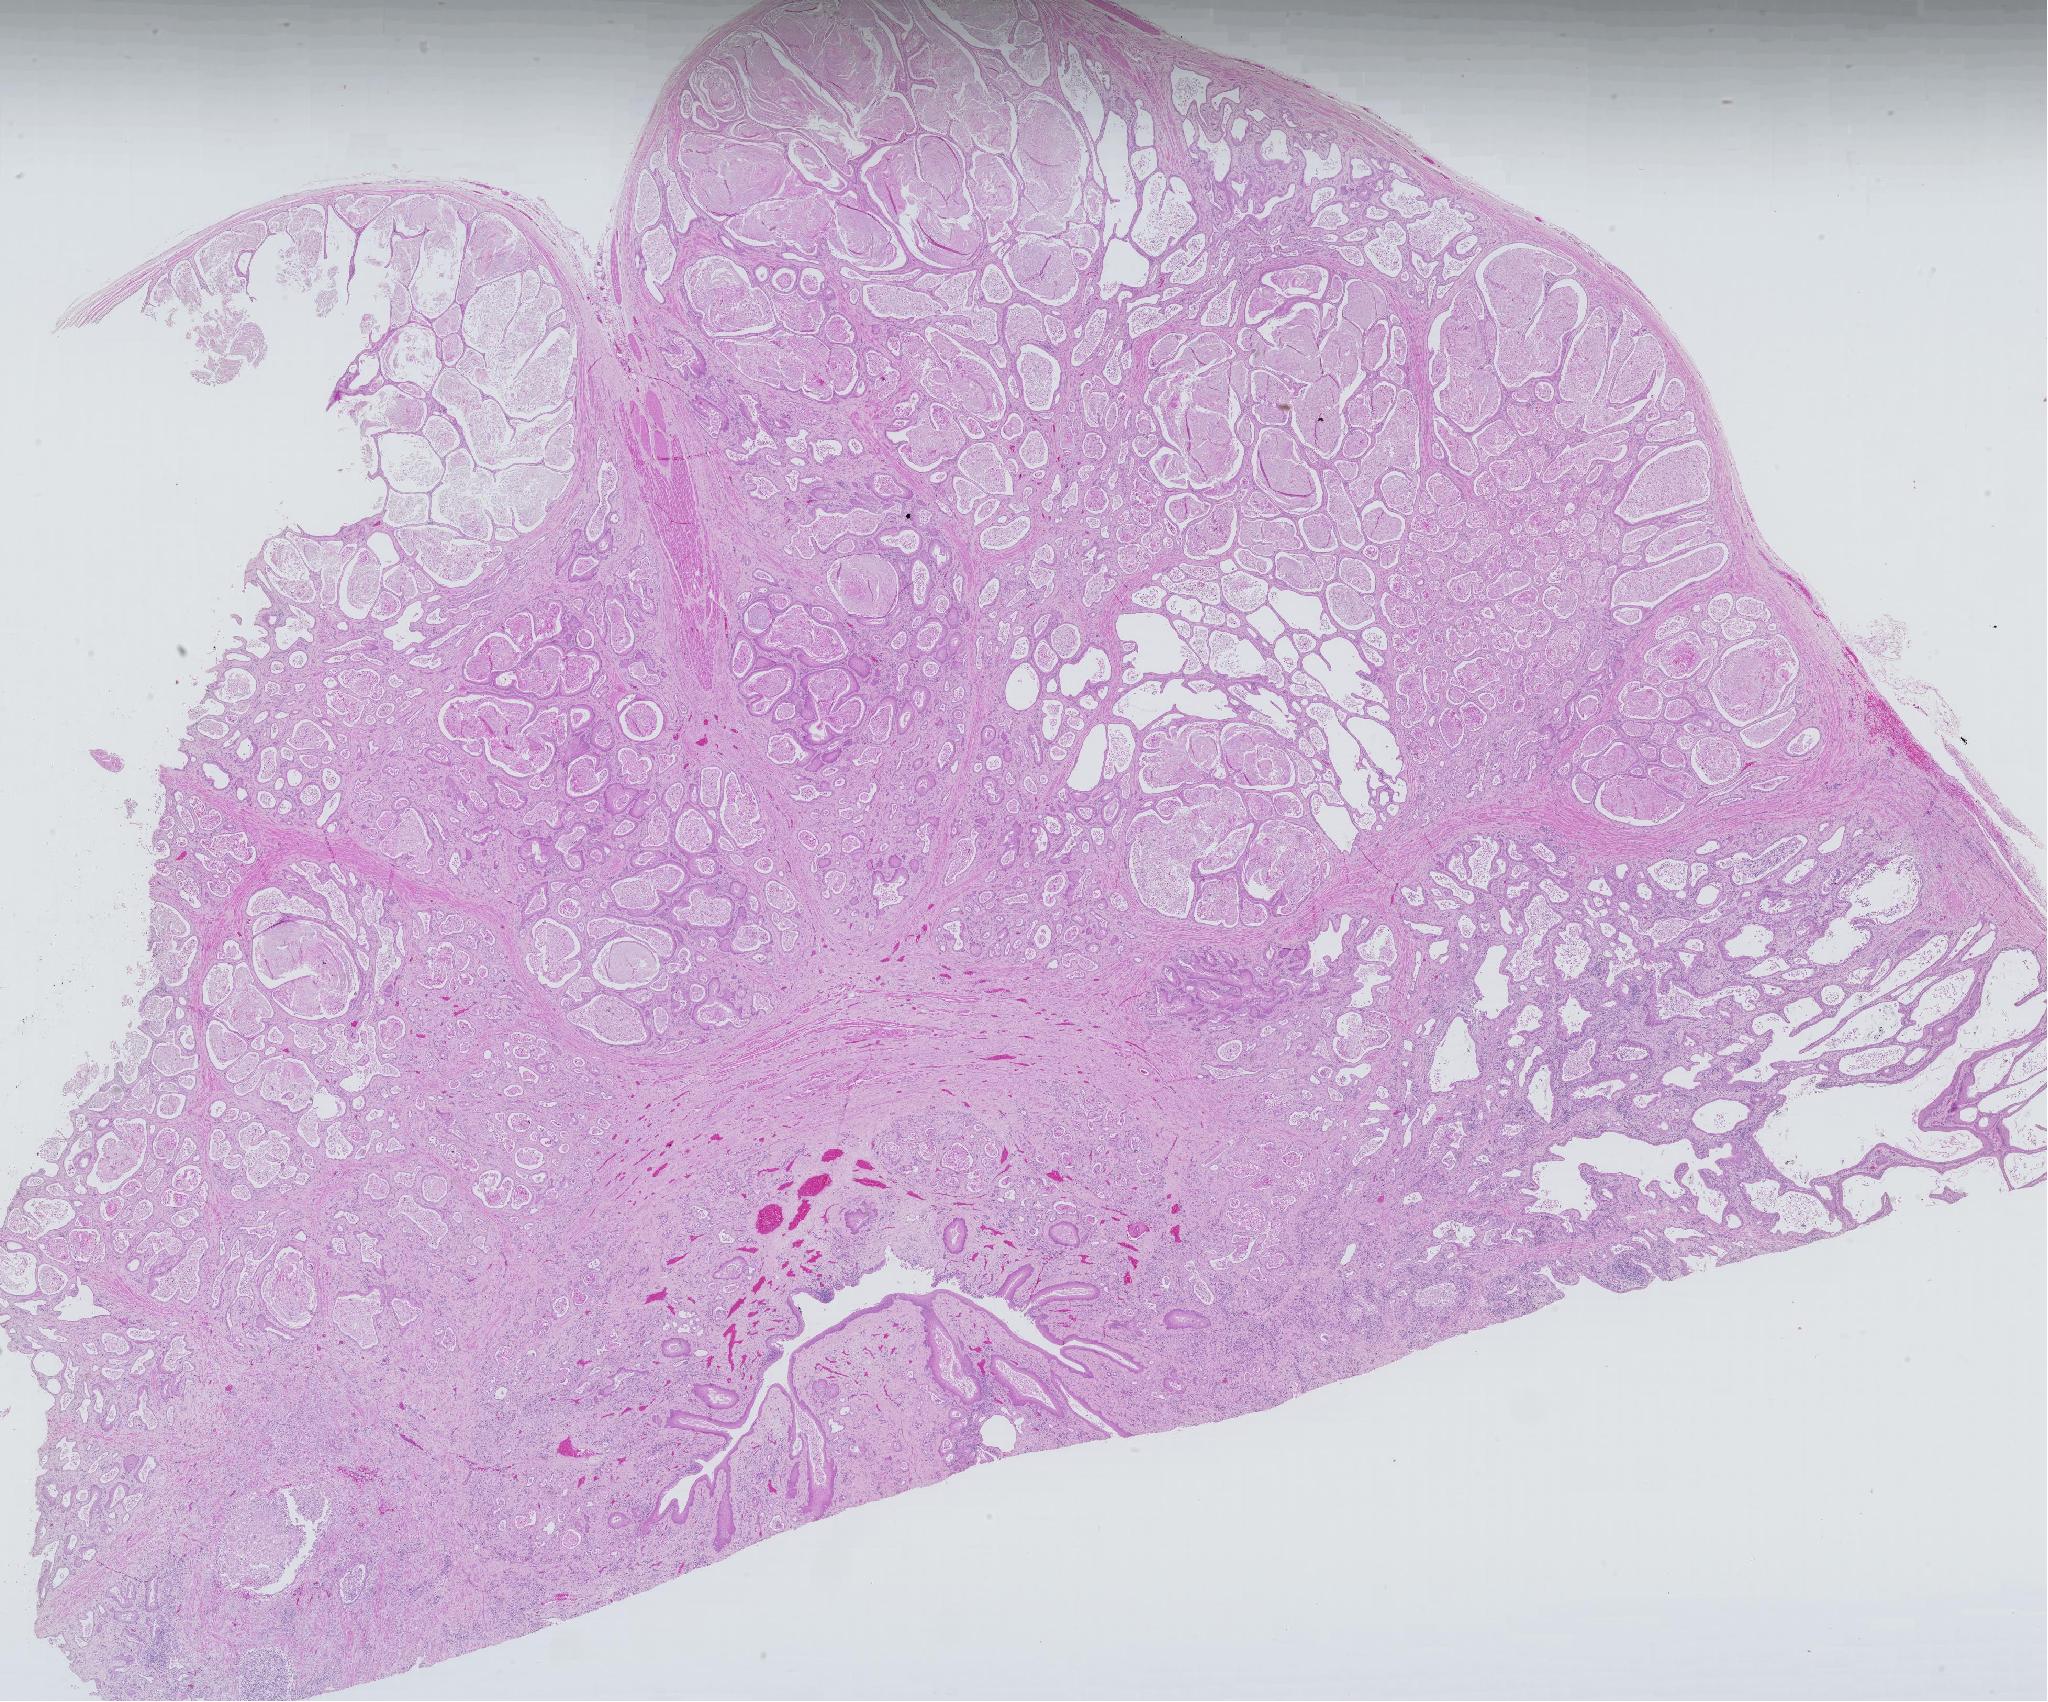

proventricle of chicken

소화기 / / 조류

선위 조직